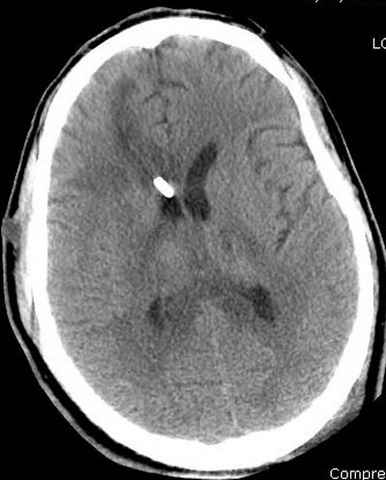

03.14.2005

больному 42, автоавария, политравма, открытая черепномозговая травма, безсознании, открытый перелом бедра, размозжение мягких тканей, дефект кожи на передней поверхности бедра около 13 см2 от ожога, компартмент синдром.

По поводу открытого перелома больной ургентно взят на ретроградное интрамедулярное штифтование, после рутинного дебрайдмента и фасциотомии на бедре и на голени.

Наблюдается службой травмы и нейрохирургии (ICP) Increased Intracranial Pressure by ventricular cateter

монииторинг